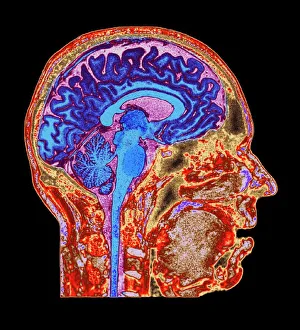

The central nervous system, the intricate network that governs our every thought and movement, is a marvel of complexity. From the delicate cerebellum tissue to the detailed light micrograph capturing its essence, we are reminded of its importance in maintaining balance and coordination. Anatomy comes alive as we explore the human brain from an inferior view. The intricacy of brain fibers is revealed through DTI MRI scans like C017/7099 and C017/7035, showcasing their vital role in transmitting information throughout this extraordinary organ. Artistic renderings bring us closer to understanding the medulla oblongata's significance within the brain. Its portrayal in various artworks allows us to appreciate how it controls essential functions such as breathing and heart rate. As we delve deeper into studying the central nervous system, models of the human brain provide invaluable insights into its structure and organization. Lateral views reveal countless regions responsible for cognition, emotion regulation, sensory perception, and motor control. Microscope slides offer glimpses into nerve cells' intricate architecture—a testament to their ability to transmit electrical signals at lightning speed. Meanwhile, glial stem cell cultures captured under a light microscope remind us of their crucial role in supporting neuronal function. Finally, artistic representations unveil the limbic system's enigmatic nature—an interconnected web responsible for emotions and memory formation. These captivating artworks allow us to visualize this complex network within our brains. Exploring these hints provides a glimpse into the awe-inspiring world of our central nervous system—the very foundation upon which our thoughts, actions, memories reside—reminding us just how remarkable our brains truly are.